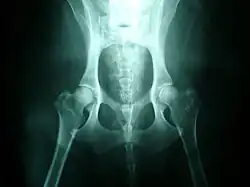

La gravedad de la displasia se puede medir si trazamos el denominado ángulo de Norberg. Éste consiste en trazar sobre una radiografía una línea que vaya desde el centro de una cabeza del fémur, al centro de la otra. Posteriormente, desde ambos extremos se traza otra línea que pase por el borde acetabular dorsal, formando así un ángulo con la anterior. Según la amplitud del ángulo, tenemos que:

- No se presenta displasia si es mayor de 105.º.

- Si mide entre 100°-105.º, el animal tiene displasia leve.

- Si mide entre 90°-100º, la displasia es moderada. Se acompaña de enfermedad degenerativa articular y aplanamiento del acetábulo.

- Si mide menos de 90°, la displasia es grave. Puede llegar a presentar luxación.